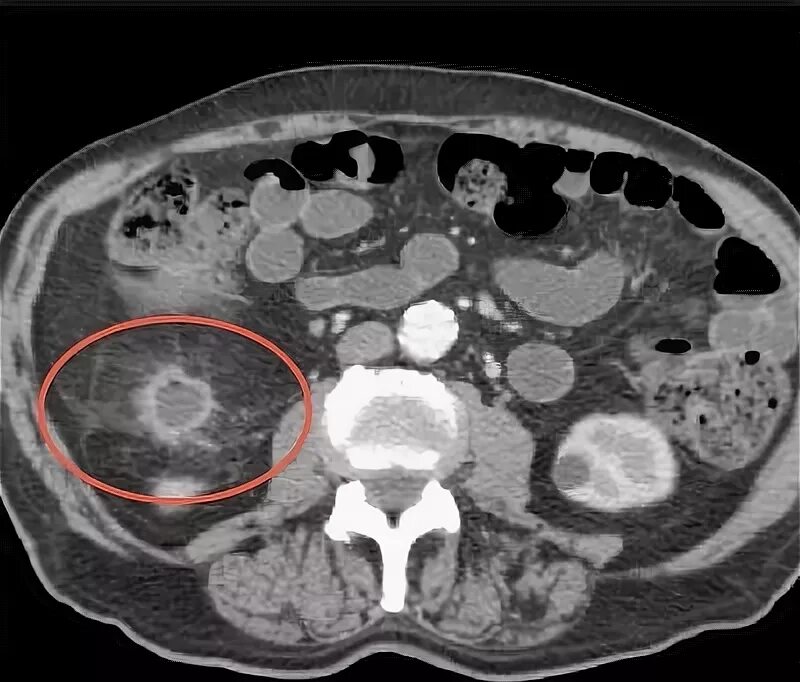

Как отличить метастазы